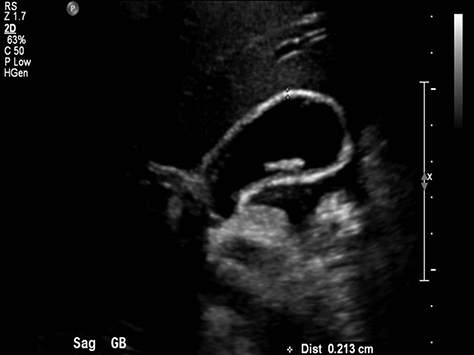

Douleur de l'abdomen avec

nausee , vomissement + image echographique de calcul

des voies biliaires ,ou de la vesicule biliaire , ce

qui entraine une diagnostic digirable de pancreatite aigue

|